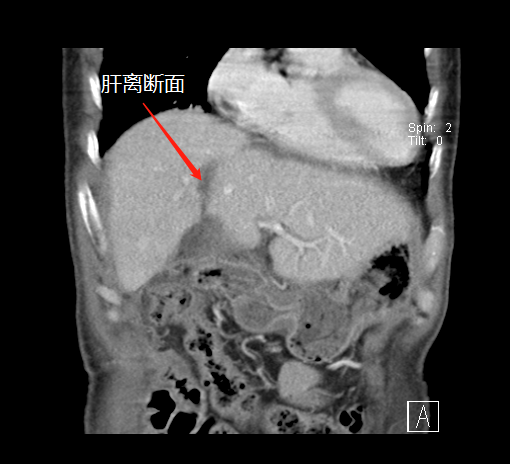

術(shù)前,左肝體積很小

第一次術(shù)后,結(jié)扎門靜脈劈開肝臟

左肝增生,第二次手術(shù)切除腫瘤

“9月底,在第一階段手術(shù)中,我們先將患者的右側(cè)門靜脈結(jié)扎(肝的血液供應(yīng)通過門靜脈和肝動脈進(jìn)行),保留肝動脈、肝靜脈和膽管的完整性,然后沿肝中裂將肝臟的左右葉徹底劈開。”據(jù)胡偉介紹,人體肝臟具有很強(qiáng)的再生功能,結(jié)扎門靜脈右支后左側(cè)肝臟由于過量的血液供應(yīng)短期內(nèi)迅速增大;同時將患者的左右肝臟離斷,降低了腫瘤侵犯左側(cè)肝臟的可能。

經(jīng)過20天左右的“養(yǎng)肝”,經(jīng)CT復(fù)查顯示,患者的左側(cè)肝臟體積已增長至42.8%,這時候,也就達(dá)到了我們說的“養(yǎng)大好肝、再切病肝”,因?yàn)榇藭r好肝已經(jīng)足以維持患者身體的運(yùn)轉(zhuǎn)需要。